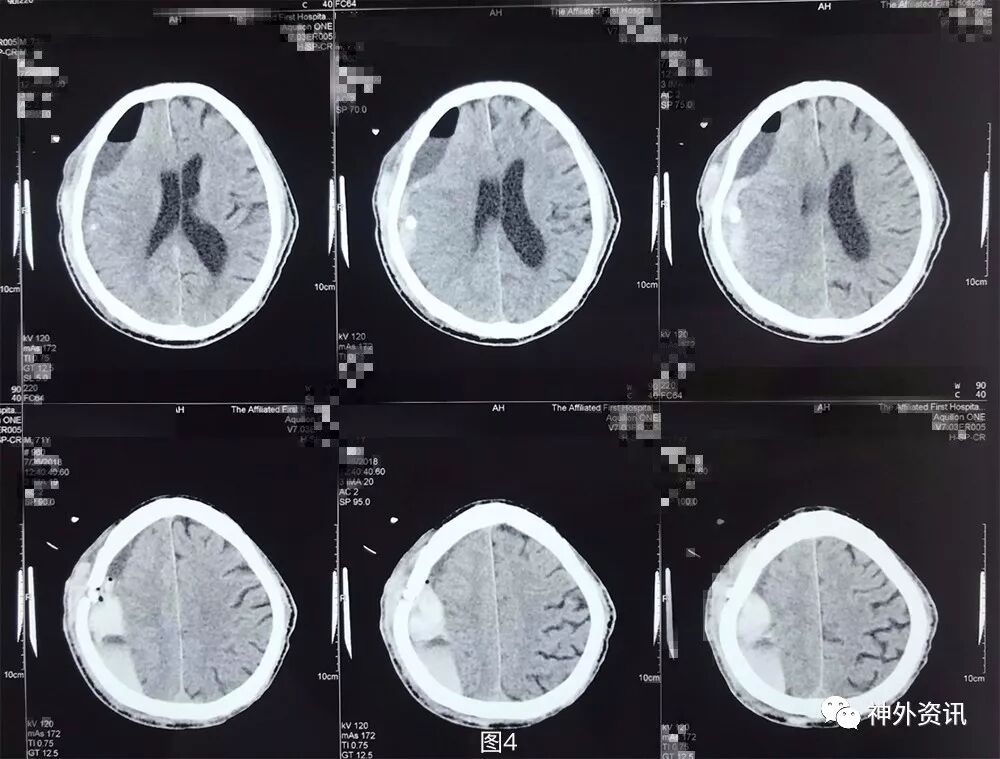

图4. 第2次手术后1天头颅CT提示:右侧额颞顶枕硬膜下血肿钻孔引流术后再次局部血肿形成。

图5. 第2次手术后4天头颅CT提示:右侧额颞顶枕硬膜下血肿局部血肿继续增大。

术后第2天复查头颅CT及MRI,提示局部仍有血肿,并见积气积液,占位较术前减少(图7)。

图7. 第三次术后第2天头颅CT及MRI提示:局部仍有血肿,可见积气积液,中线好转。

术后第3天患者出现意识变差及左肢体肌力进一步下降,查体:嗜睡,GCS14分,双侧瞳孔等大等圆,对光反应灵敏,左侧肢体肌2级,右侧肢体肌力5级,病理征未引出。急诊头颅CT提示局部积血积气积液较前片似有增多(图8)。与家属言明再次手术指征,风险及并发症等,家属要求保守,暂不手术。遂予以加用脱水药物及阿托伐他汀保守治疗。

图8. 第三次术后第3天头颅CT提示:局部积血积气积液较前片似有增多。